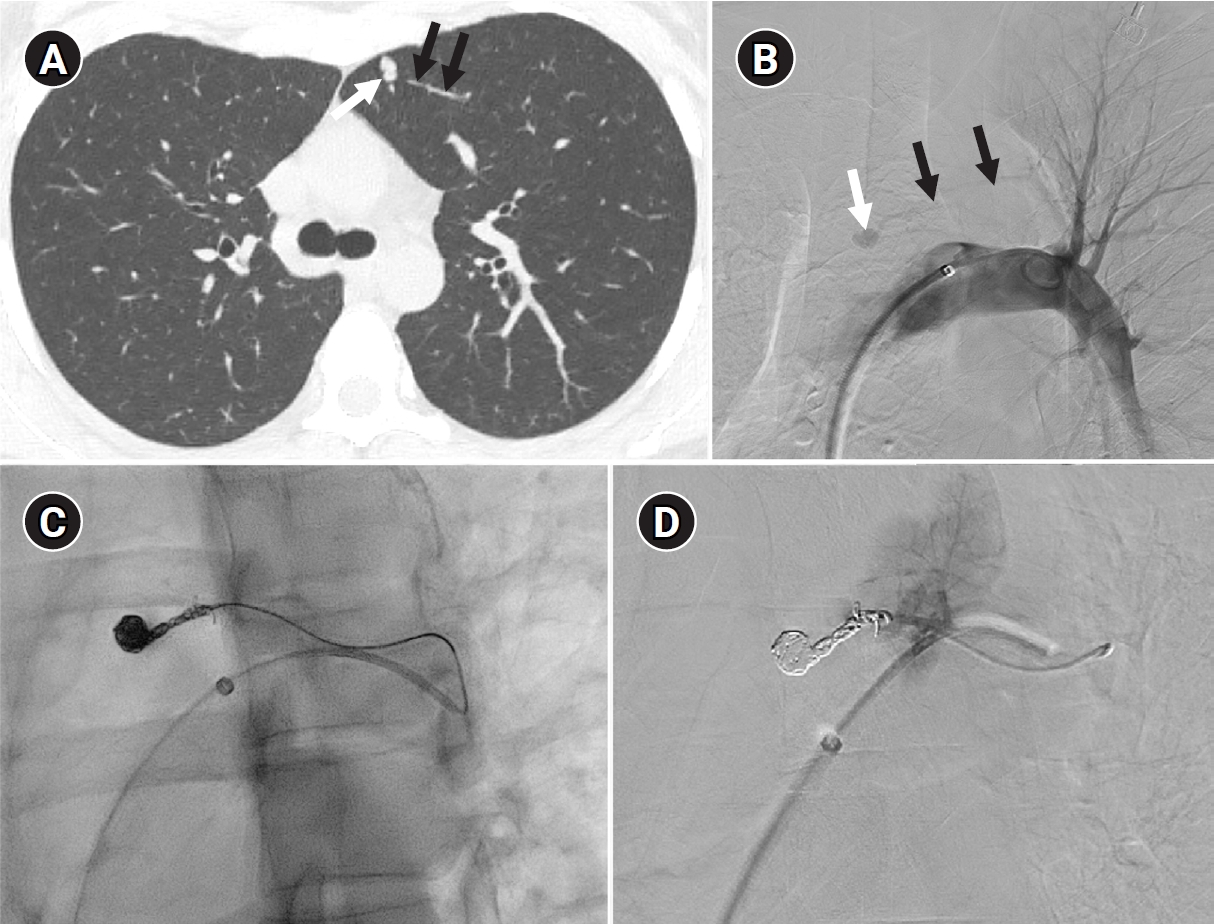

Fig. 7.

Example of a patient showing reperfusion after pulmonary arteriovenous malformation (PAVM) embolization using an Amplatzer vascular plug type IV (AVP 4). (A) Angiography of a simple-type PAVM in the right lower lobe accessed with a 5-Fr catheter. (B) Early pulmonary arterial phase image from a diagnostic angiography performed three years later due to suspected reperfusion on follow-up computed tomography, showing that the pulmonary vein is not visible distal to the AVP 4 (indicated by the arrow). (C) Delayed phase image confirming the pulmonary vein, marked by dashed arrows, which corresponds to the venous sac and draining vein seen in (A), now reduced in size. (D) A typical example of reperfusion shown on angiography using a microcatheter in an adjacent pulmonary artery, illustrating multiple newly formed tortuous collaterals leading to the draining vein (marked by dashed arrows). In this patient, additional AVP 4 embolization was performed at the tip of microcatheter (black arrow). However, draining vein size persisted even after additional treatment (not shown).

kjir-2026-00010f7.jpg